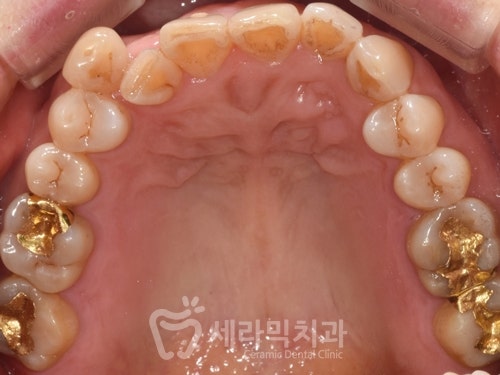

50대 치아교정전후 사례

오늘 살펴볼 50대 치아교정전후

사례의 주인공은 50대 후반 여성분으로

삐뚤빼뚤한 치열과,

앞니의 반대교합을 개선하고 싶어서

교정을 시작하셨습니다.

(1) 50대 치아교정전후 사례자 프로필

▶️ 교정 시작 나이 : 50대 후반

▶️ 교정 시작 이유 : 치열불규칙

▶️ 예상 교정 기간 : 15~18개월

▶️ 치료방법 : 비발치, 세라믹교정

(2) 문제점 분석, 진단

① 치열불규칙

② 앞니 반대교합

③ 아래턱 돌출 경향